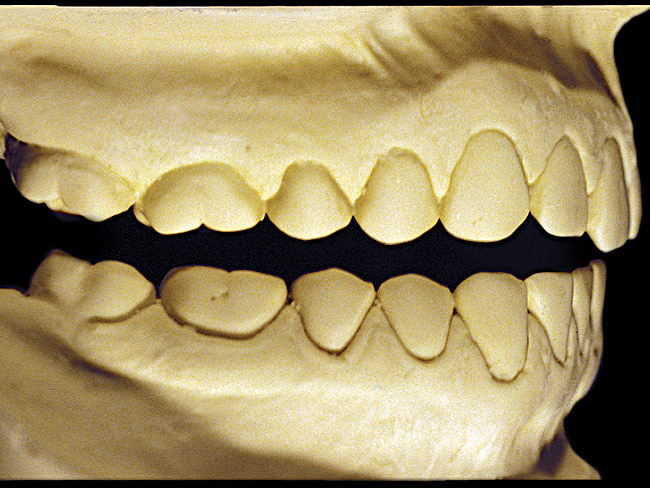

Figure 4  Advanced NCLTS from bruxism, maxillary arch.

Figure 4

The patient shown in Figure 3 and Figure 4 exhibited severe NCLTS from bruxism. Examination of the casts indicated that the NCLTS was progressively greater toward the anterior teeth. Cupping and cratering was not present because there was no secondary cause. Figure 5 and Figure 6 detail another bruxism patient, but to a lesser degree and one with cupping/cratering caused by toothpaste. The cups or craters were not caused from bruxism because the teeth could not touch the bottom of the invaginations. In both featured patients, upon hand-articulating the casts, the NCLTS facets matched up and the diagnosis of bruxism was confirmed.